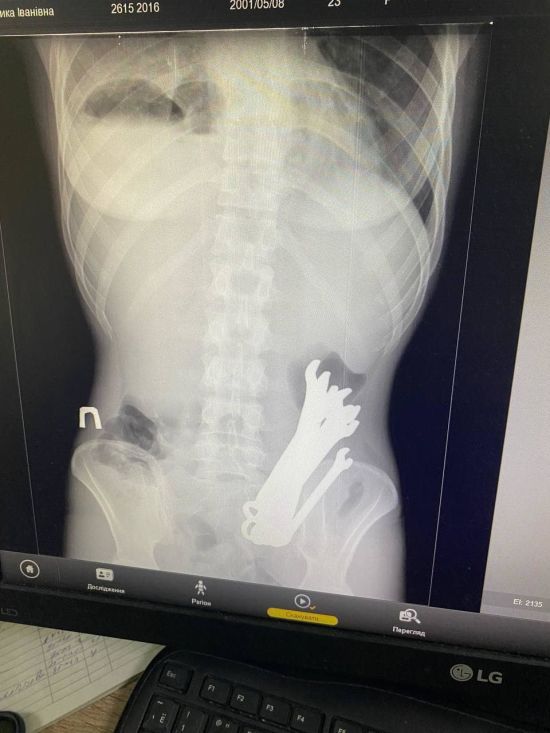

У тілі українця виявили шість гайкових ключів: як вони там опинилися та чим це закінчилося (фото)

У Черкасах медики дістали з тіла українця шість гайкових ключів, які він проковтнув. Про це повідомили представники відділення торакальної хірургії